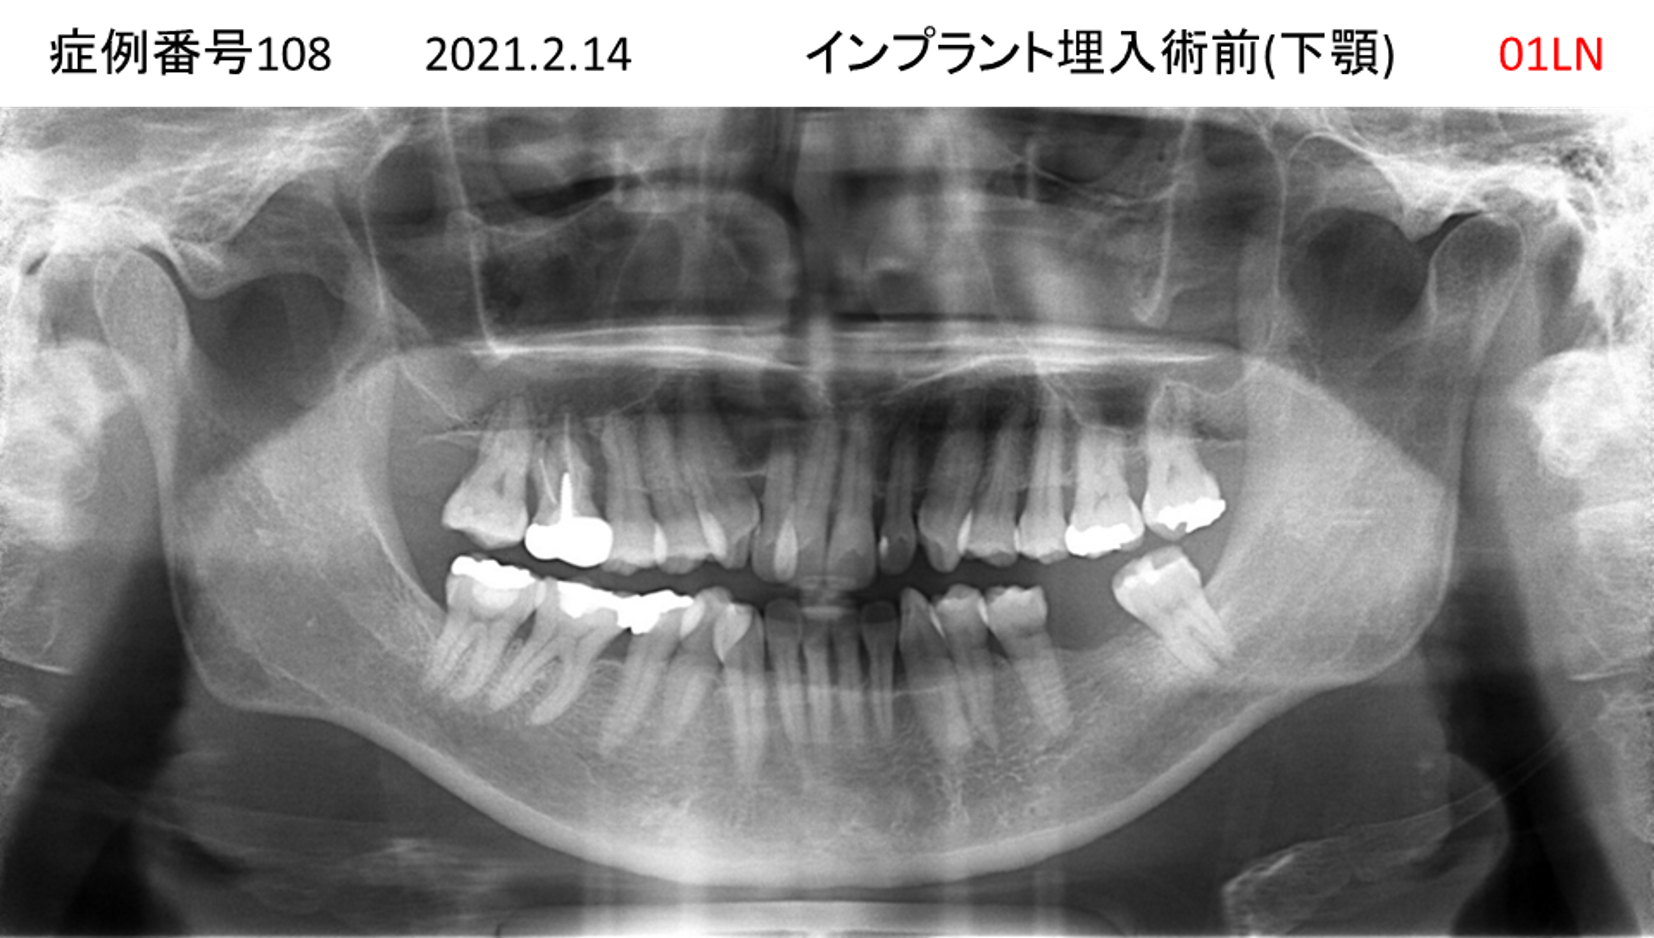

左下の歯が痛い患者様のインプラント症例

| 治療名称 |

インプラント |

| 治療費用 |

330万円+税 |

| 治療期間 |

4か月 |

| 患者さんの症状(主訴) |

左下の歯が痛い |

| 治療内容 |

サイナスリフト 抜歯即時インプラント |

| 治療結果 |

食事に困らない。見た目がとても良くなった。 |

| 治療の注意点(リスク/副作用) |

インプラントが壊れたら再治療が必要 |